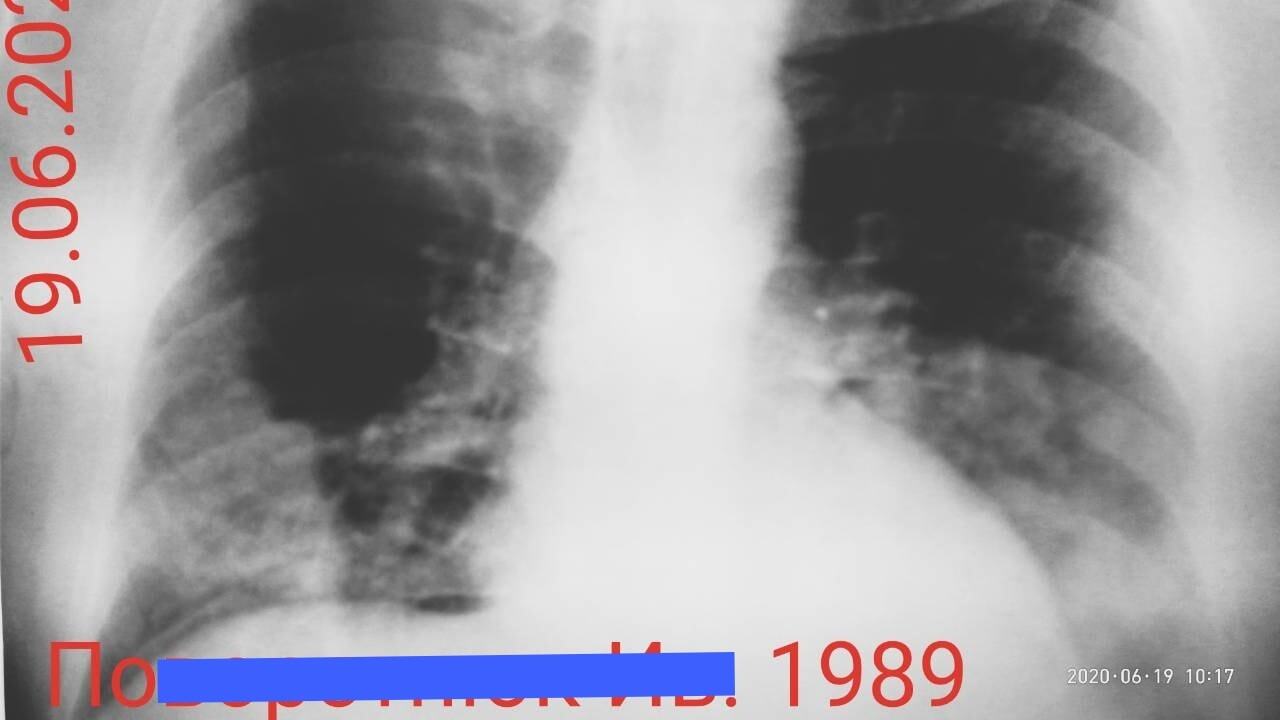

Журналист канала "24 Украина" Андрей Булгаров обнародовал снимки людей, у которых подтверждена коронавирусная инфекция COVID-19.

На снимках, обнародованных на его странице в Facebook, показаны последствия влияния вируса на легкие

"Меня задолбало пояснять на словах всяким неверующим в COVID-19, что все на самом деле очень серьезно. Поэтому попросил папу, который давно на пенсии, но продолжает работать в районной больнице врачом-рентгенологом, прислать мне снимки больных, у которых официально подтверждён COVID-19. В общем, вот как коронавирус постепенно съедает легкие. А если по научному, вызывает двустороннюю полисегментарную пневмонию", – пояснил написал Булгаров.